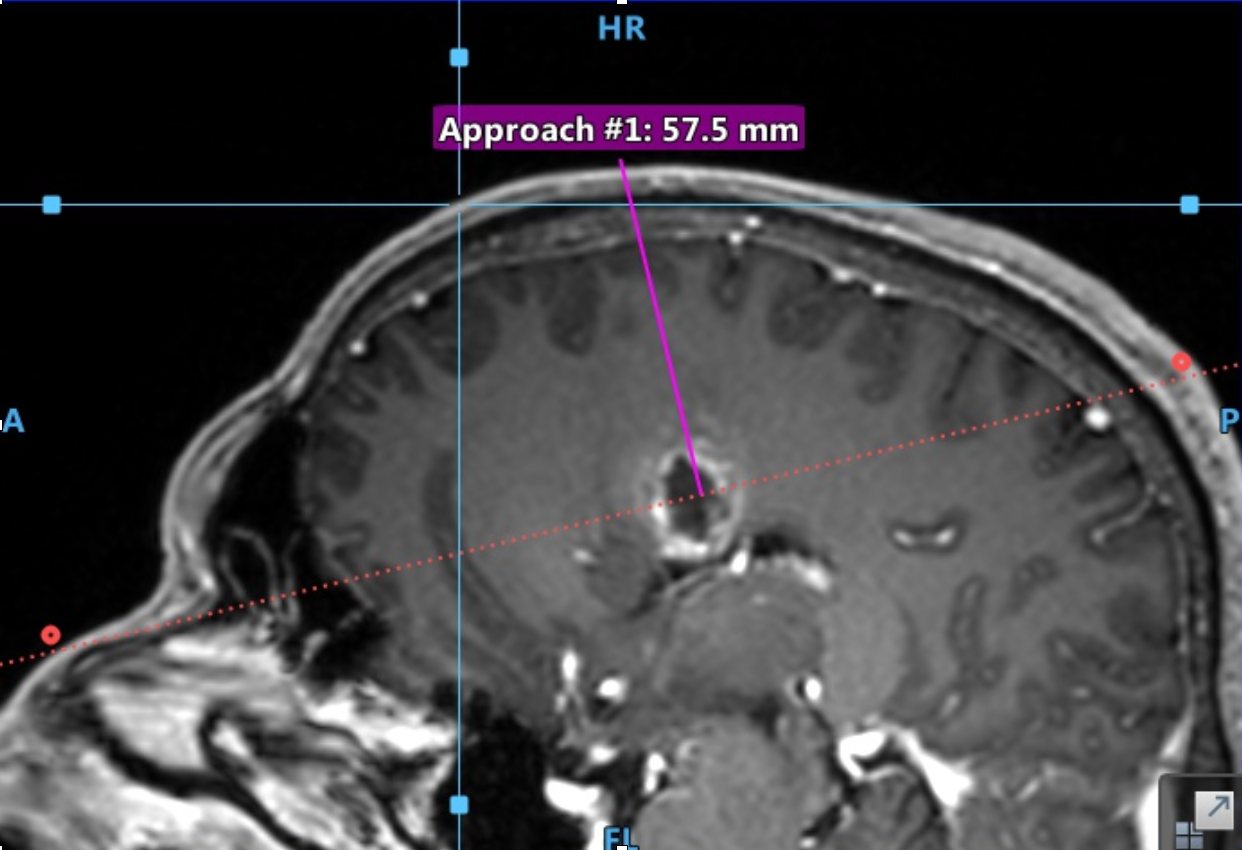

Ce presupune o biopsie ghidată prin neuronavigație? Se utilizează un RMN obișnuit, cu secțiuni fine, la 1-2 mm. (protocol 3D), pe care să fie vizibilă tumora (de obicei T1 cu contrast sau FLAIR). Acest RMN va funcționa ca o hartă pe care o încărcăm în stația de neuronavigație – GPS-ul -, iar corelarea dintre hartă și situația din teren – pacientul anesteziat – se face cu un instrument asemănător unui creion sau arătător (pointer). După ce avem o corelație bună între imaginea 3D și pacient (eroarea medie este de 0,9 – 1 mm.), se folosește un pointer special atașat de acul de biopsie care ne permite să navigăm cu precizie și să prelevăm țesut tumoral de unde dorim, urmărind poziția vârfului acului în timp real pe ecranul stației de neuronavigație.

Această metodă este mult mai comodă decât sterotaxia, atât pentru pacient, care nu mai este nevoit să stea cu cadrul fixat pe cap, cât și pentru chirurg, care nu mai trebuie să calculeze coordonatele țintei și să le transpună pe cadrul de sterotaxie. În ceea ce privește precizia, fiind o metodă “free-hand”, este mai puțin performantă decât biopsia streotaxtică, însă suficient de precisă pentru 99% dintre tumorile cerebrale. În plus, există brațe mobile care permit fixarea poziției acului de biopsie astfel încât să obținem precizia maximă, atunci când avem o tumoră mică, localizată în profunzime.

De regulă, o biopsie ghidată prin neuronavigație durează o oră, cu tot cu anestezie, iar spitalizarea este de 24 ore (o noapte). Se face un control postoperator prin computer-tomograf nativ (ne interesează o eventuală complicație, de ex. sângerare). Avantajul biopsiei în cazul tumorilor sau al pacienților inoperabili este că durează puțin, este minim-invazivă și, printr-o corectă alegere a traiectoriei, permite obținerea unui diagnostic cu riscuri foarte reduse.